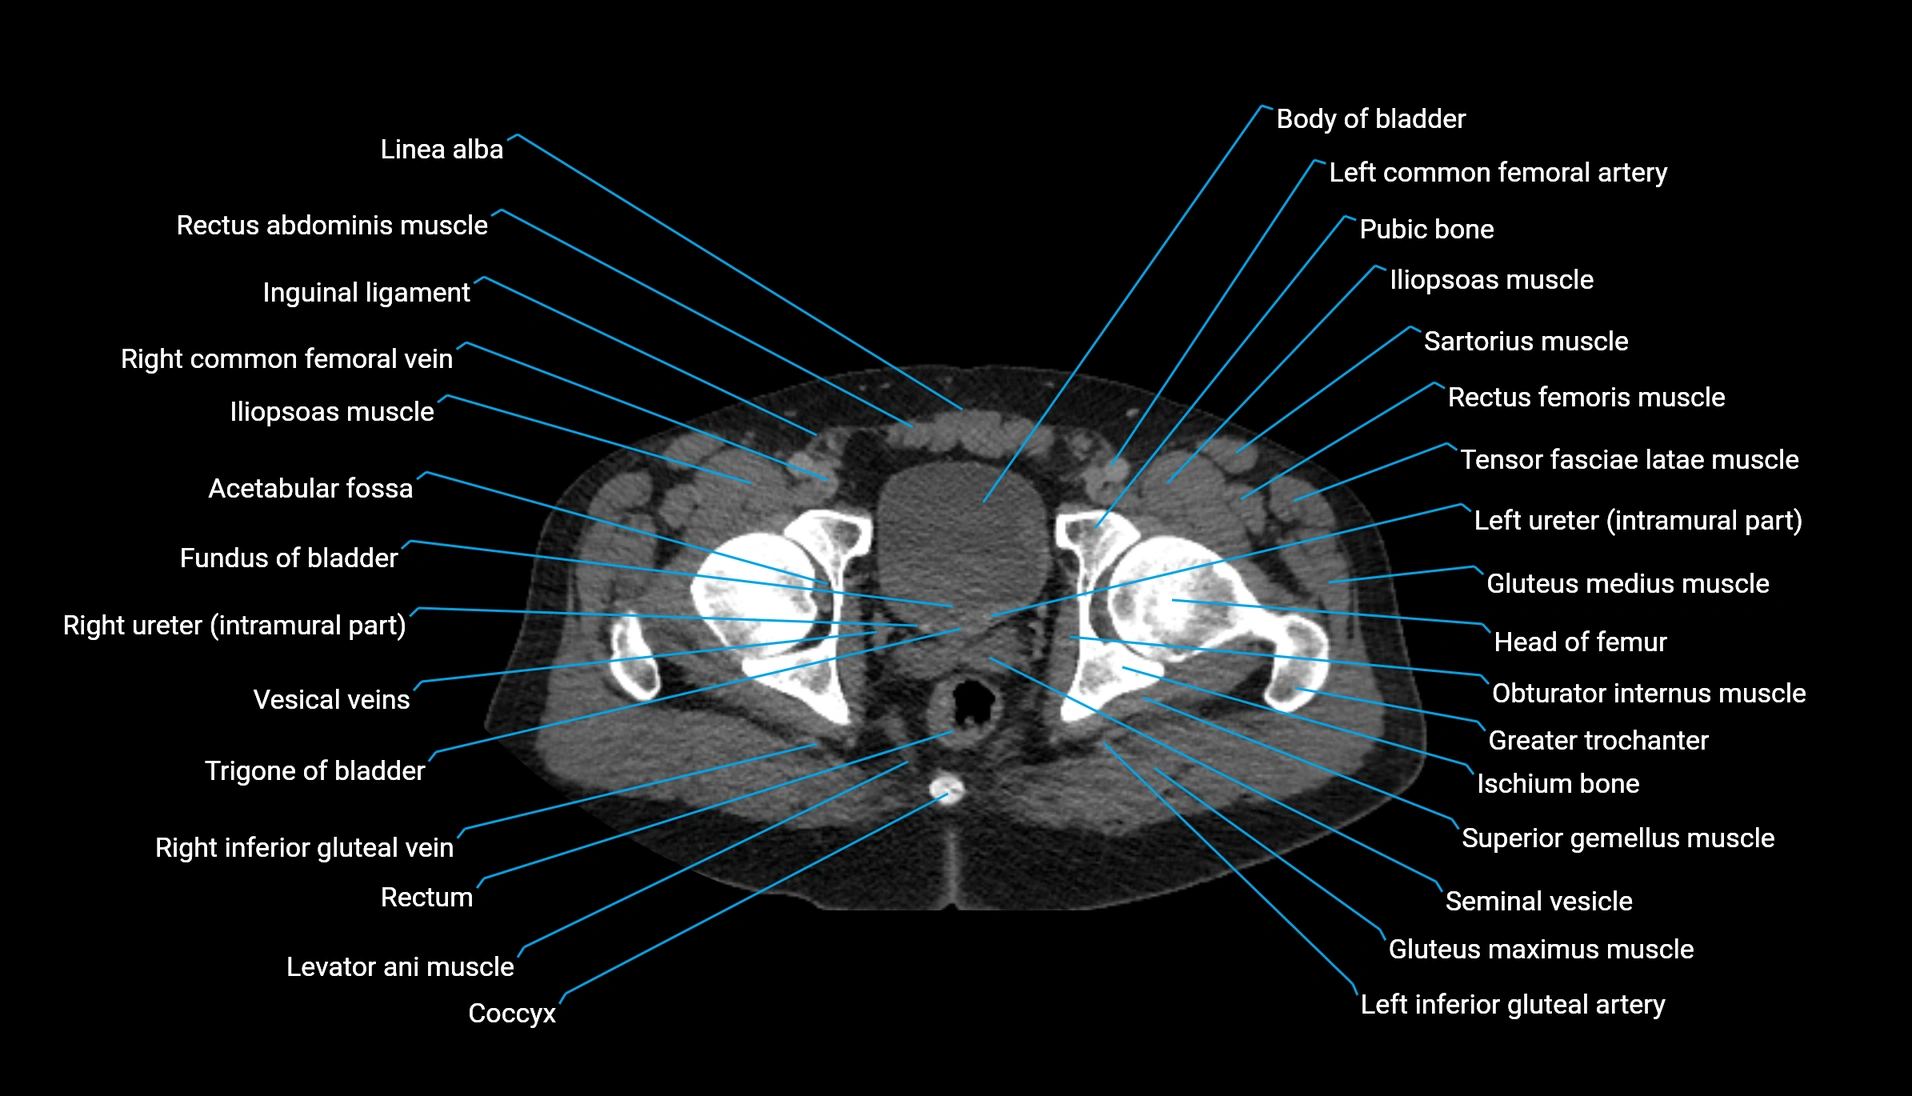

The acetabular margin, also called the acetabular rim, is the bony edge of the acetabulum, the cup-shaped cavity on the lateral aspect of the pelvis that articulates with the head of the femur to form the hip joint. The acetabular margin consists of the superior, anterior, and posterior borders of the acetabulum and is interrupted inferiorly by the acetabular notch.

The rim provides attachment for the acetabular labrum, a fibrocartilaginous structure that deepens the acetabulum, increasing hip joint stability. The transverse acetabular ligament bridges the acetabular notch, completing the bony ring. Superiorly, the margin bears the greatest load during standing and gait, making it the most common site of degenerative changes.

The acetabular margin is clinically significant in femoroacetabular impingement (FAI), acetabular fractures, hip dysplasia, and osteoarthritis. Its morphology (depth, coverage, and orientation) is a key factor in hip biomechanics and surgical planning, especially in arthroscopy and hip preservation surgery.

CT Appearance

Non-contrast CT:

-

Demonstrates cortical bone of acetabular rim in excellent detail

Detects fractures, dysplasia, retroversion, or bony overcoverage (pincer impingement)

3D reconstructions used in preoperative hip surgery planning

CT VRT 3D image

CT image